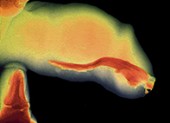

© ISM/SOVEREIGN/MEdICAL IMAGES X-RAY SHOWING CANCER OF THE GLANS PENIS ANd URETHRA

• Penile SCC is an uncommon cancer affecting mostly uncircumcised older men that is increasing in the developed world.